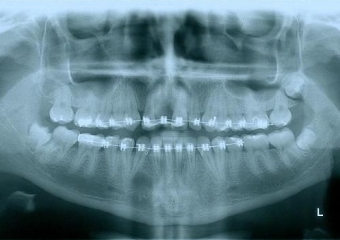

Raio - x Inicial 2013